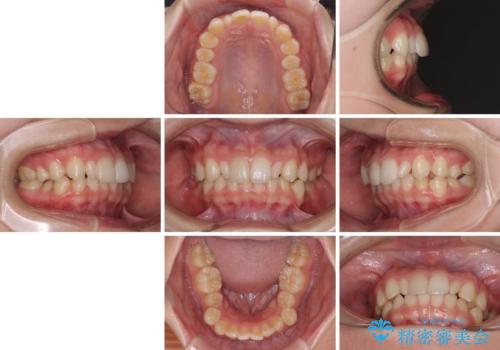

- 歯列のデコボコを気にして来院された患者様です。

安価に速やかに治療をしたいとのことで、メタルワイヤーにより矯正治療を行うこととしました。

上顎左右側切歯は矮小歯であり、矯正治療開始前にオールセラミッククラウンによる形態修正を兼ねた補綴治療を提案しましたが、特に気にならないとのことで、歯冠形態はそのままとしました。